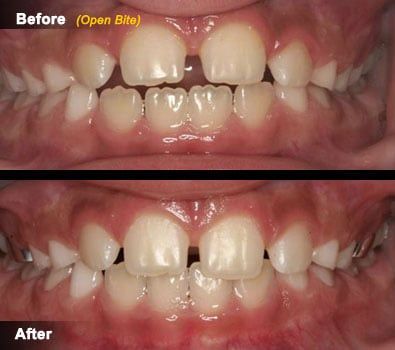

Open Bite and Cross Bite

These are two common problems in children that have their origin in discrepancies between the size of the jaws (top and bottom), or discrepancies between the size of the teeth and the amount of space available.

- Anterior open bites refer to a condition in which the top and bottom front teeth are not in contact (they do not touch each other when the patient bites). The origins of open bites can be traced to habits that patients have or had in the past, and occasionally to discrepancies between the sizes of the jaws. Since most open bites in children are associated to an existing habit, treatment usually addresses the habit itself and is most effective when done at an early age. Many appliances are available for treating this condition and your dentist will discuss in detail the risks and benefits of treating an open bite in children.